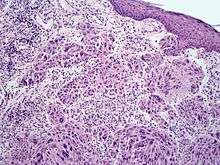

Melanoma with features of a Spitz nevus (also known as a "Spitzoid melanoma") is a cutaneous condition characterized histologically with tissue similar to a spitz nevus and with overall symmetry and a dermal nodule of epithelioid melanocytes that do not mature with progressively deeper dermal extension.[1]